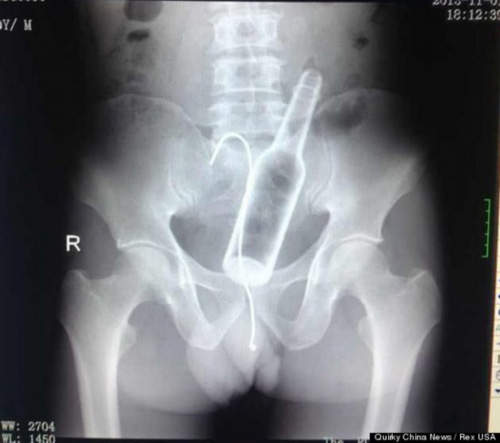

話說看大叔一開始就插的這麼帶勁,深怕哪天手一滑不然就是送太大力...整個進去怎麼辦><